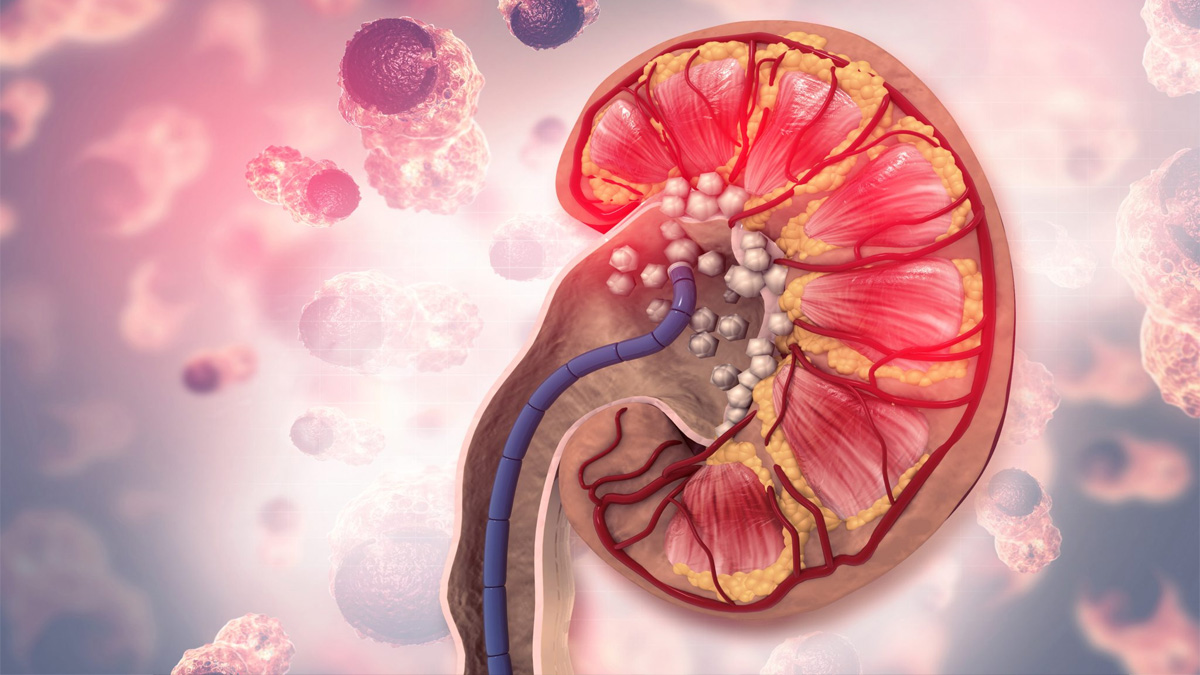

কিডনিতে পাথর হয় মূলত যখন প্রস্রাবে থাকা কিছু খনিজ পদার্থ, যেমন ক্যালসিয়াম, অক্সালেট বা ইউরিক অ্যাসিড জমে গিয়ে শক্ত হয়ে যায়। এতে মূত্রে থাকা পানি এগুলোকে যথেষ্ট পরিমাণে ভাঙতে পারে না বলে জমাট বাঁধে। এই পাথর কিডনির ভিতরে বা বের হওয়ার পথে চলাচলের সময় তীব্র ব্যথা সৃষ্টি করতে পারে।

প্রতি ১১ জনে ১ জনের কিডনিতে পাথর হতে পারে। পুরুষদের এই সমস্যা হওয়ার সম্ভাবনা নারীদের চেয়ে দ্বিগুণ। তবে আশার কথা হলো, কিছু নিয়ম-কানুন মেনে চললে এর প্রতিরোধ সম্ভব এবং এ রোগের ভালো চিকিৎসাও আছে।